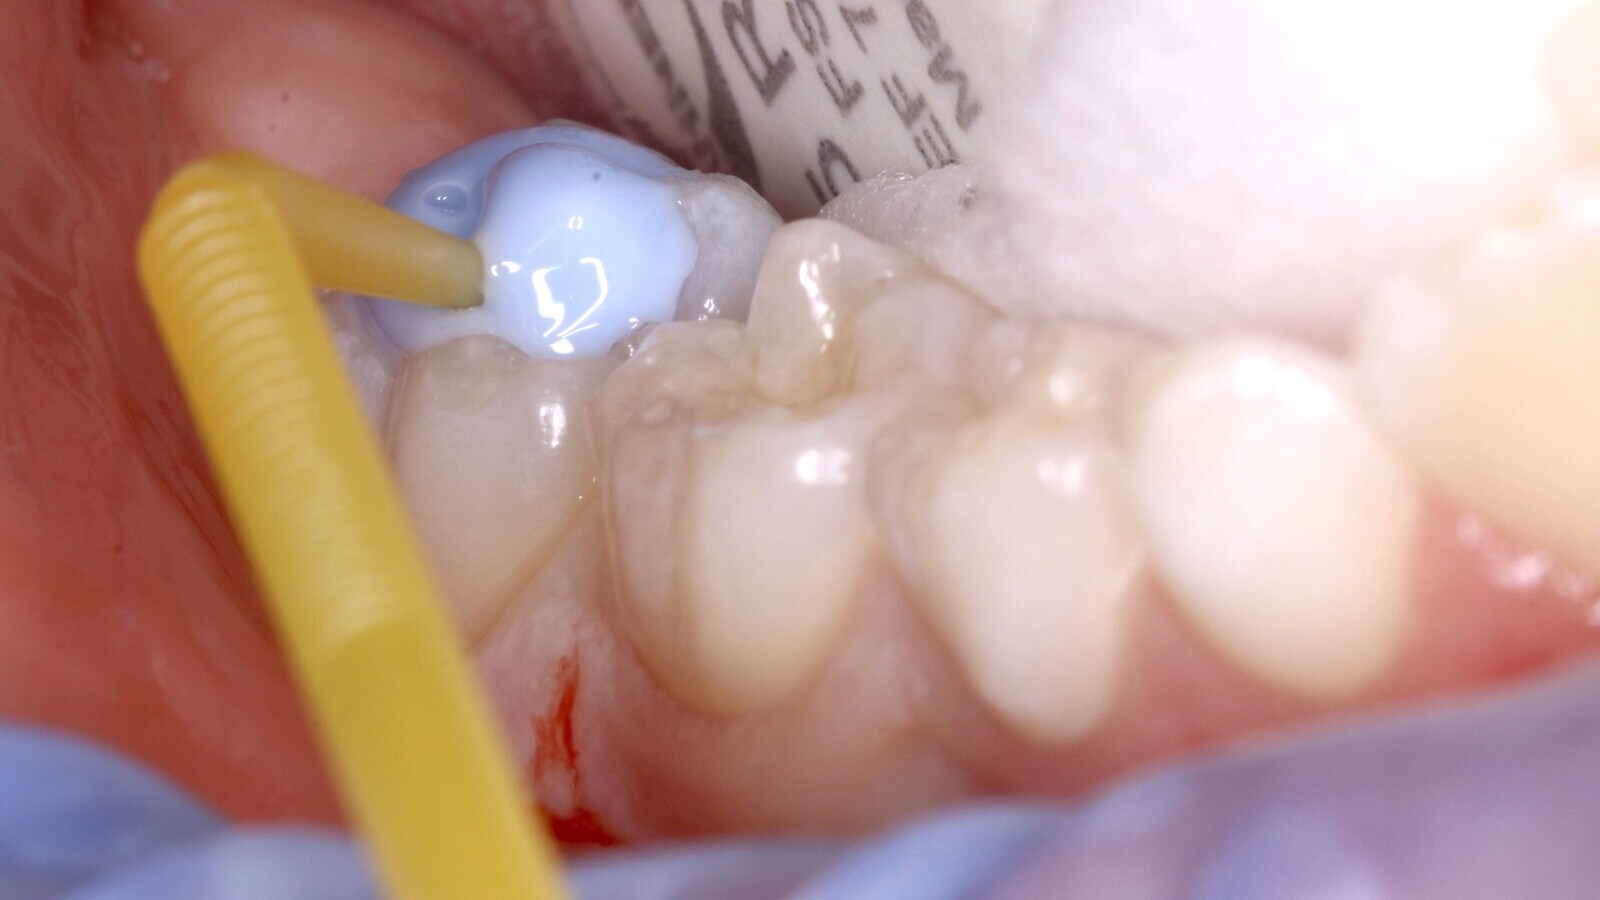

Antes de proceder con la limpieza de la cavidad, se toma una impresión de la anatomía con un material de barrera gingival (Gingival Barrier, SDI Ltd.) fijado en un micro-aplicador (Fig. 4), de forma que se pueda copiar la anatomía existente mediante la técnica del estampado oclusal (Fig. 5). Tras realizar la apertura de la cavidad (Fig. 6) se inicia la remoción selectiva del tejido cariado con una estrategia químico-mecánica (Fig. 7) hasta llegar a DENTINA FIRME en la base y dura en la periferia de la cavidad (Fig. 8) bajo aislamiento relativo utilizando Optragate (Ivoclar Vivadent) y rollos de algodón, se procede a aplicar el material restaurador EQUIA Forte fil (Fig. 9).

Fig. 9. Se procede a aplicar el material restaurador EQUIA Forte fil.

El material se extruye dentro la cavidad luego de realizar la mezcla durante 10 segundos y colocando la cápsula en un dispensador (Fig. 10) que permite aplicar el material desde el piso hasta los márgenes de la cavidad en un solo incremento. Inmediatamente, tras haber aplicado vaselina líquida con un pincel sobre la impresión oclusal, se procede al estampado. Posteriormente al fraguado inicial (2 - 3 minutos), se retira la copia oclusal y se eliminan los excesos que se extruyeron hacia los lados utilizando un instrumento manual (Carver, LM Arte) (Fig. 11). Se remueven los restos de vaselina y se aplica el EQUIA Forte Coat sobre la superficie del material para luego polimerizar durante 20 segundos (Fig. 12). Se realiza el control de oclusión y se da de alta a la paciente con la recomendación de evitar consumir alimentos duros por las próximas horas (Fig. 13).